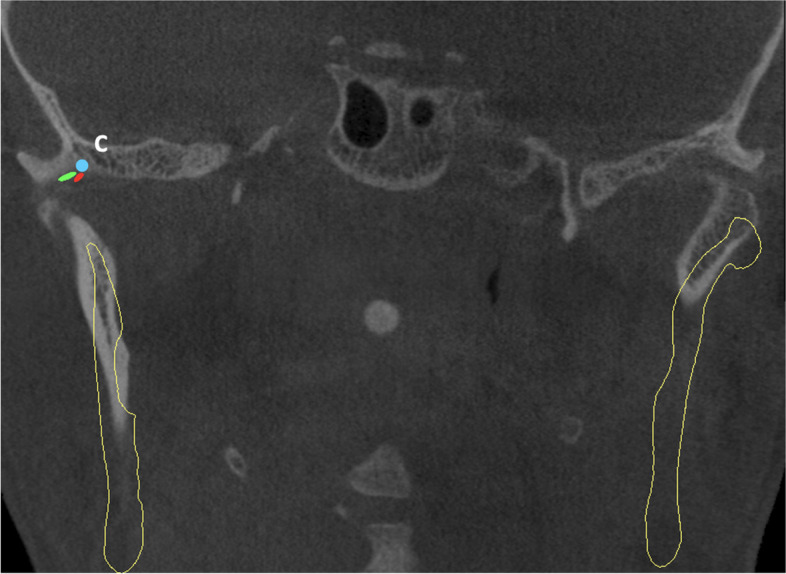

Background: This study aimed to investigate the range of angles and depths necessary for effective entry into the TMJ using CBCT images, focusing on classical Holmlund Hellsing points and a two-needle approach.

Methods: A retrospective cohort of CBCT images from January 2020 to November 2023 was analysed using 3D analysis to determine the variance in the required angles and depths.

Results: The average age of the 68 participants included in the study was 29.5 ± 11.1, 58.8% of the participants were female and 41.2% were male. The anterior needle measurements showed a relatively low standard deviation(SD) in depth(SD:3.6) with a low variance coefficient(12.5%), whereas the axial and coronal angles exhibited greater variability(SD:9.1 and 7.6, respectively). For the posterior needles, moderate SDs in depth(SD:3.5) and greater variabilities in axial and coronal angles(SD:9.6 and 5.3, respectively) were observed. A weak negative correlation was observed between the axial angle of the posterior needle and age(p: 0.028, Pearson r: -0.29) Anterior needle depth (p:0.037) and posterior needle axial angle(p:0.014) were greater in males than females. The anterior needle depth in patients with temporamandibular disease was greater than in those without(p:0,03).

Conclusion: There were significant differences in the angle measurements for both anterior and posterior needles, but lower variance in depth. The depths and angles of the needles did not correlate with age.